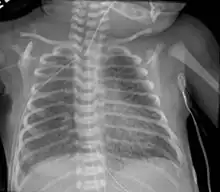

| Micrograph of an emphysematous lung; emphysema is a rare respiratory disease, strongly associated with smoking. H&E stain. | |